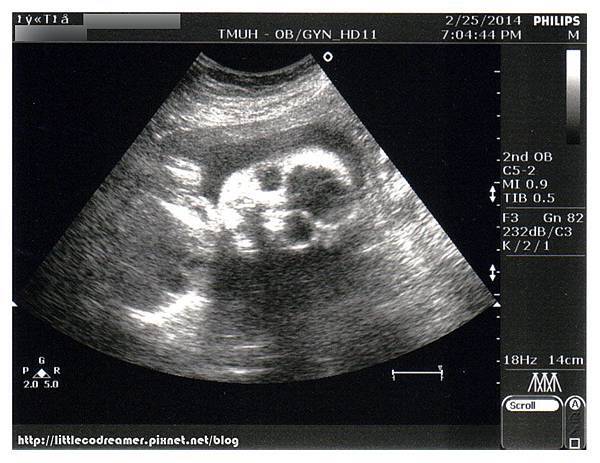

為了節省待在醫院的時間,等待抽血的空檔進行超音波檢查。這一次超音波是孕期中健保唯一給付。原本應該在第20週照,但當時安排了高層次超音波,所以就擺到24週產檢再使用。

健保給付超音波屬於標準檢查,看得細節比平時產檢自費照的還要多,花費的時間也比較久。檢驗師知道我的週數第一句話便問:「糖水喝完沒?幾分喝完的?」因為她要協助我控制時間,好讓我來得及抽血。北醫婦產科門診在二樓,抽血檢驗區在一樓,檢驗師貼心到連我走去的腳程都算在裡面。

小CO一切生長指數都正常,羊水量、胎盤、子宮頸長度也都正常。雖然胎位還沒轉正,但30週前都還會再轉。這一次檢驗師印給醫生看的照片有十多張,送了我二張。

↑這是孕期產檢超音波照中難得的露臉照。因為之後不是手擋、腳丫擋,就是乾脆背對著不給看。

↑雖然是給我二張,感覺好像只是角度相同,遠近不同而已。